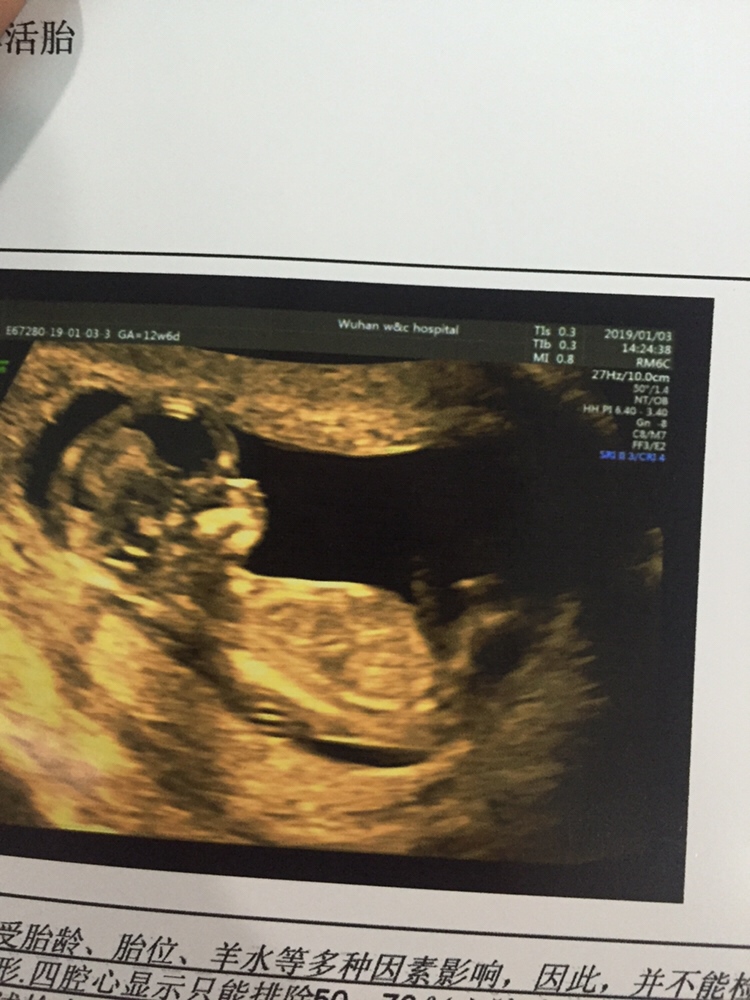

孕12周+2天

NT都包括哪些项,还是只做B超

Ww-zaw[帖主]:加强版b超

下次c超再上图,12.13周左右很模糊,14周后可以准确看出!

孕12周+6天

男宝宝,恭喜!

Ww-zaw[帖主]:这么小都能看出男宝女宝了呀